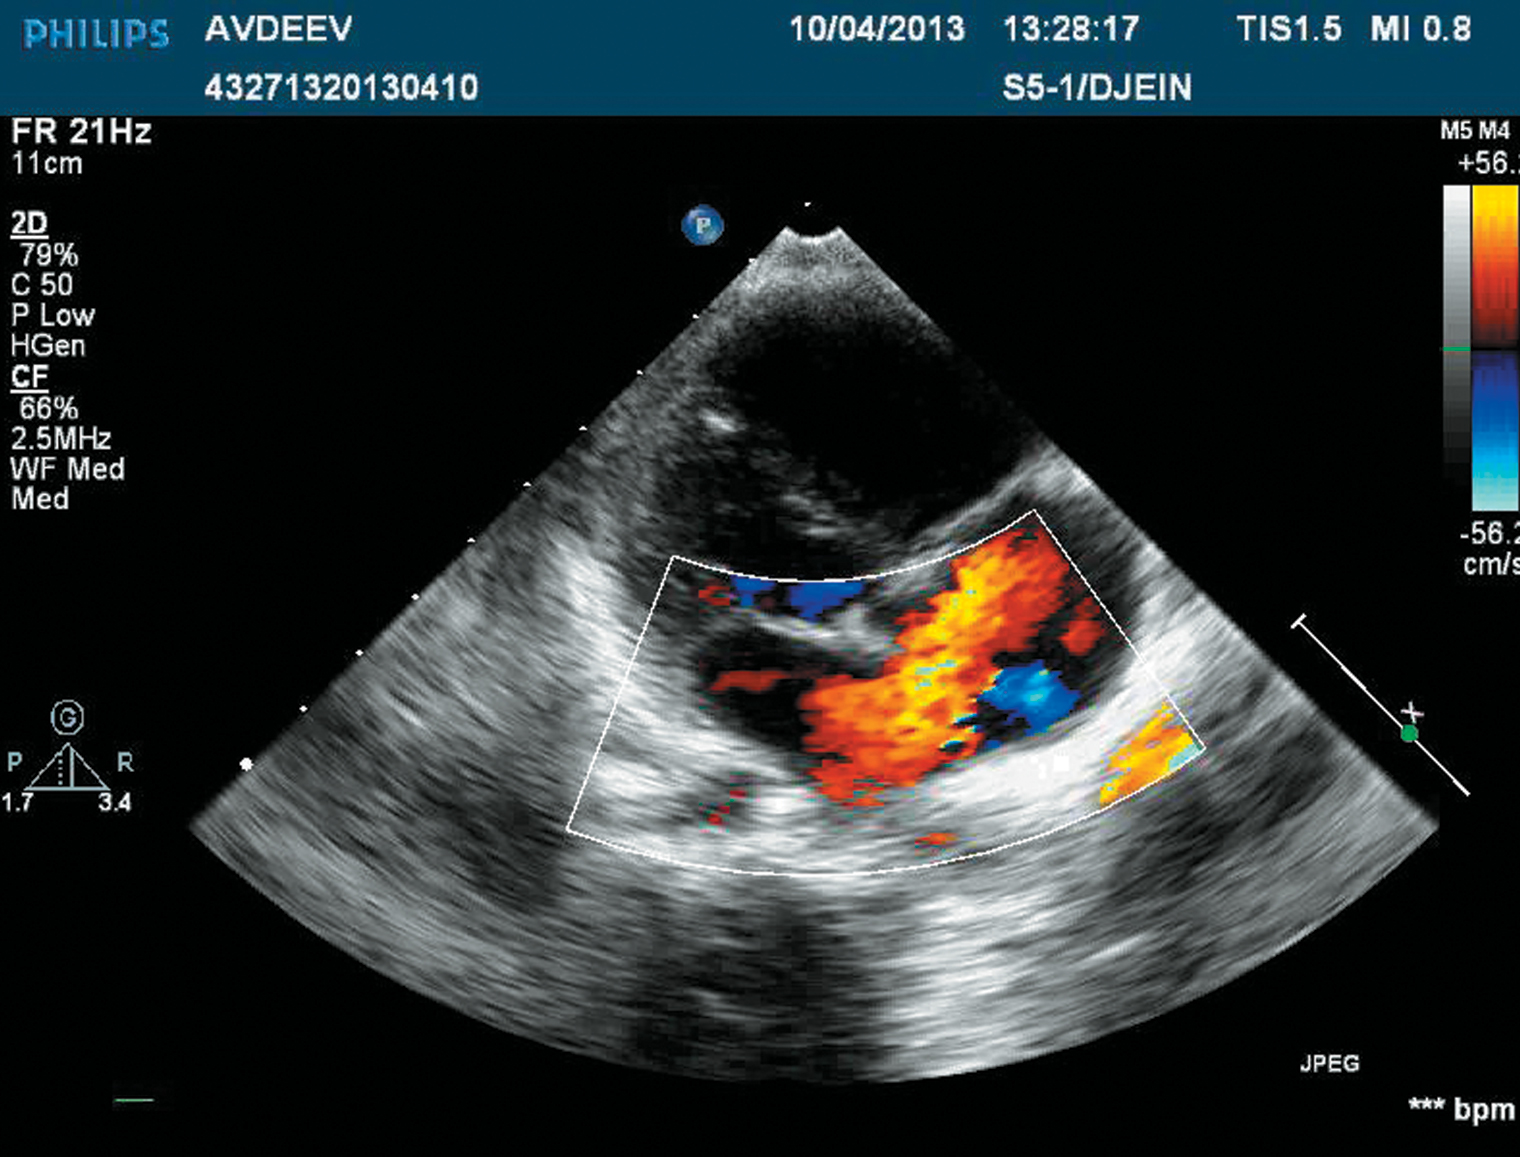

Ультразвуковое исследование сердца, или эхокардиография, — основной метод диагностики дефекта межпредсердной перегородки. На УЗИ можно увидеть отверстие между предсердиями, а в специальном режиме — как кровь из одного перетекает в другое.

Обычно УЗИ сердца проводят через грудную клетку. Но бывает, что дефект в этом случае не виден, а явное подозрение на него есть. Тогда сделают чреспищеводное УЗИ, когда специальный ультразвуковой зонд вводят в пищевод через рот. Он располагается близко к сердцу, поэтому изображения получаются более четкими. Процедуру можно выполнить под седацией.